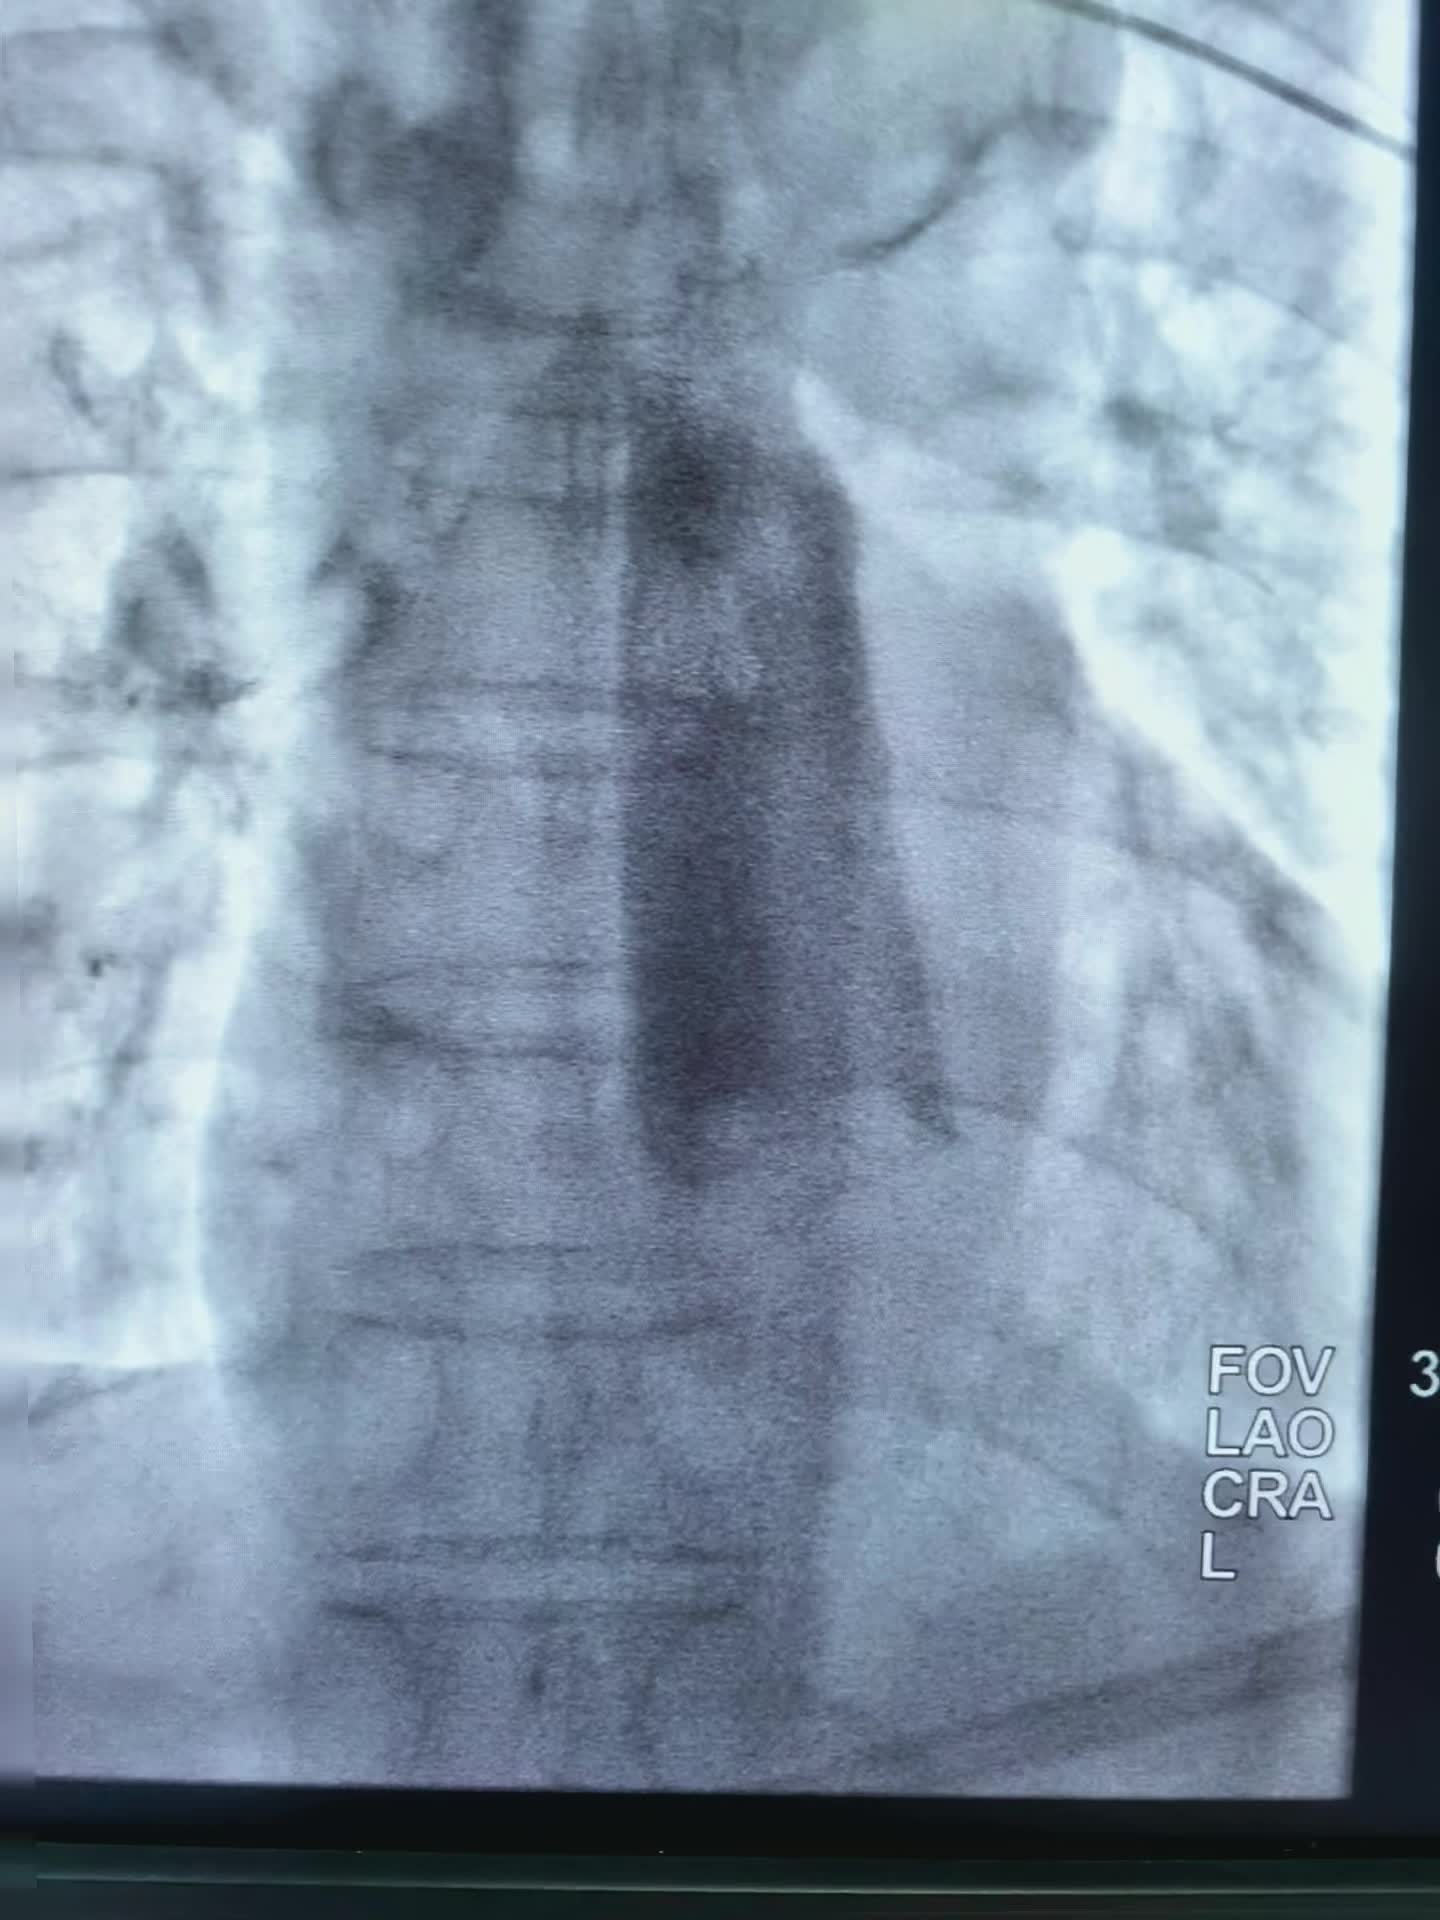

一例贲门癌患者经三年化疗及靶向治疗病情进展!贲门及胃底管壁增厚血供丰富,贲门管腔完全被肿瘤占据合并旰胃间隙淋巴结转移融合!今日行贲门区及转移淋巴结载药微球栓塞及鼻十二指肠管置入! 2024-06-10 19:37

上周做的一例贲门癌老年患者,对静脉化疗病变不敏感,化疗后恶心呕吐无力症状重,而切病灶有进展增大。患者拒绝在次静脉化疗。家属了解了可以通过动脉入路超选择直达供肿瘤动脉,灌注化疗栓塞术。化疗药物用量小,浓度大,做用强而切可以阻断肿瘤供血。一个小针眼,局麻下进行,术后反应不明显。疗效确切,患者易接受!希望有一个好的疗效! 2024-05-26 00:57